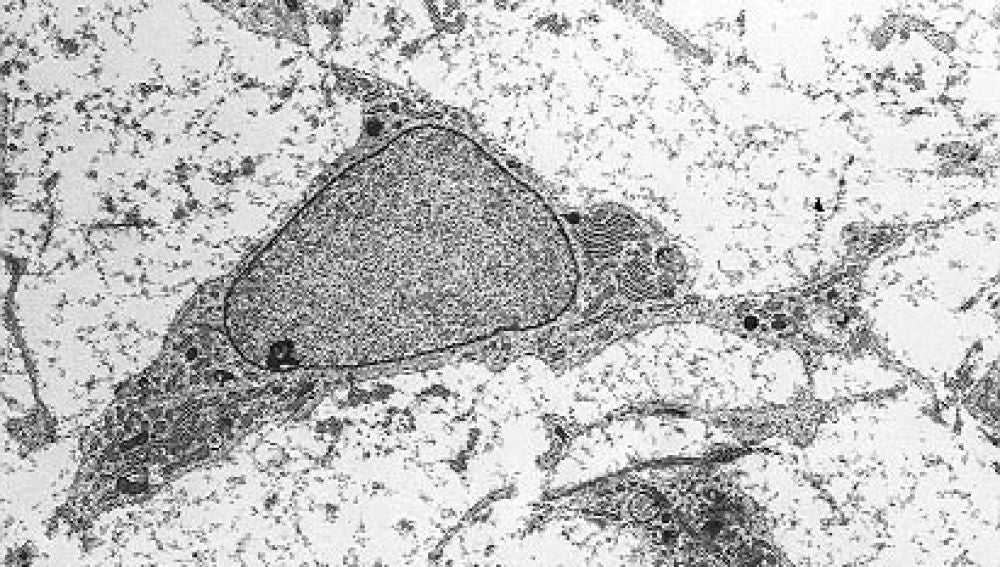

Células madre mesenquimales Sinc

Estudios previos en animales y humanos habían sugerido el potencial de las células madre mesenquimales de la médula ósea, también conocidas como células estromales o MSC –por sus siglas en inglés– en el tratamiento del lupus, ya que se considera que la enfermedad puede ser producto de una alteración en el tejido mesenquimal, aquel que da lugar, por ejemplo, a huesos, músculos o cartílagos.